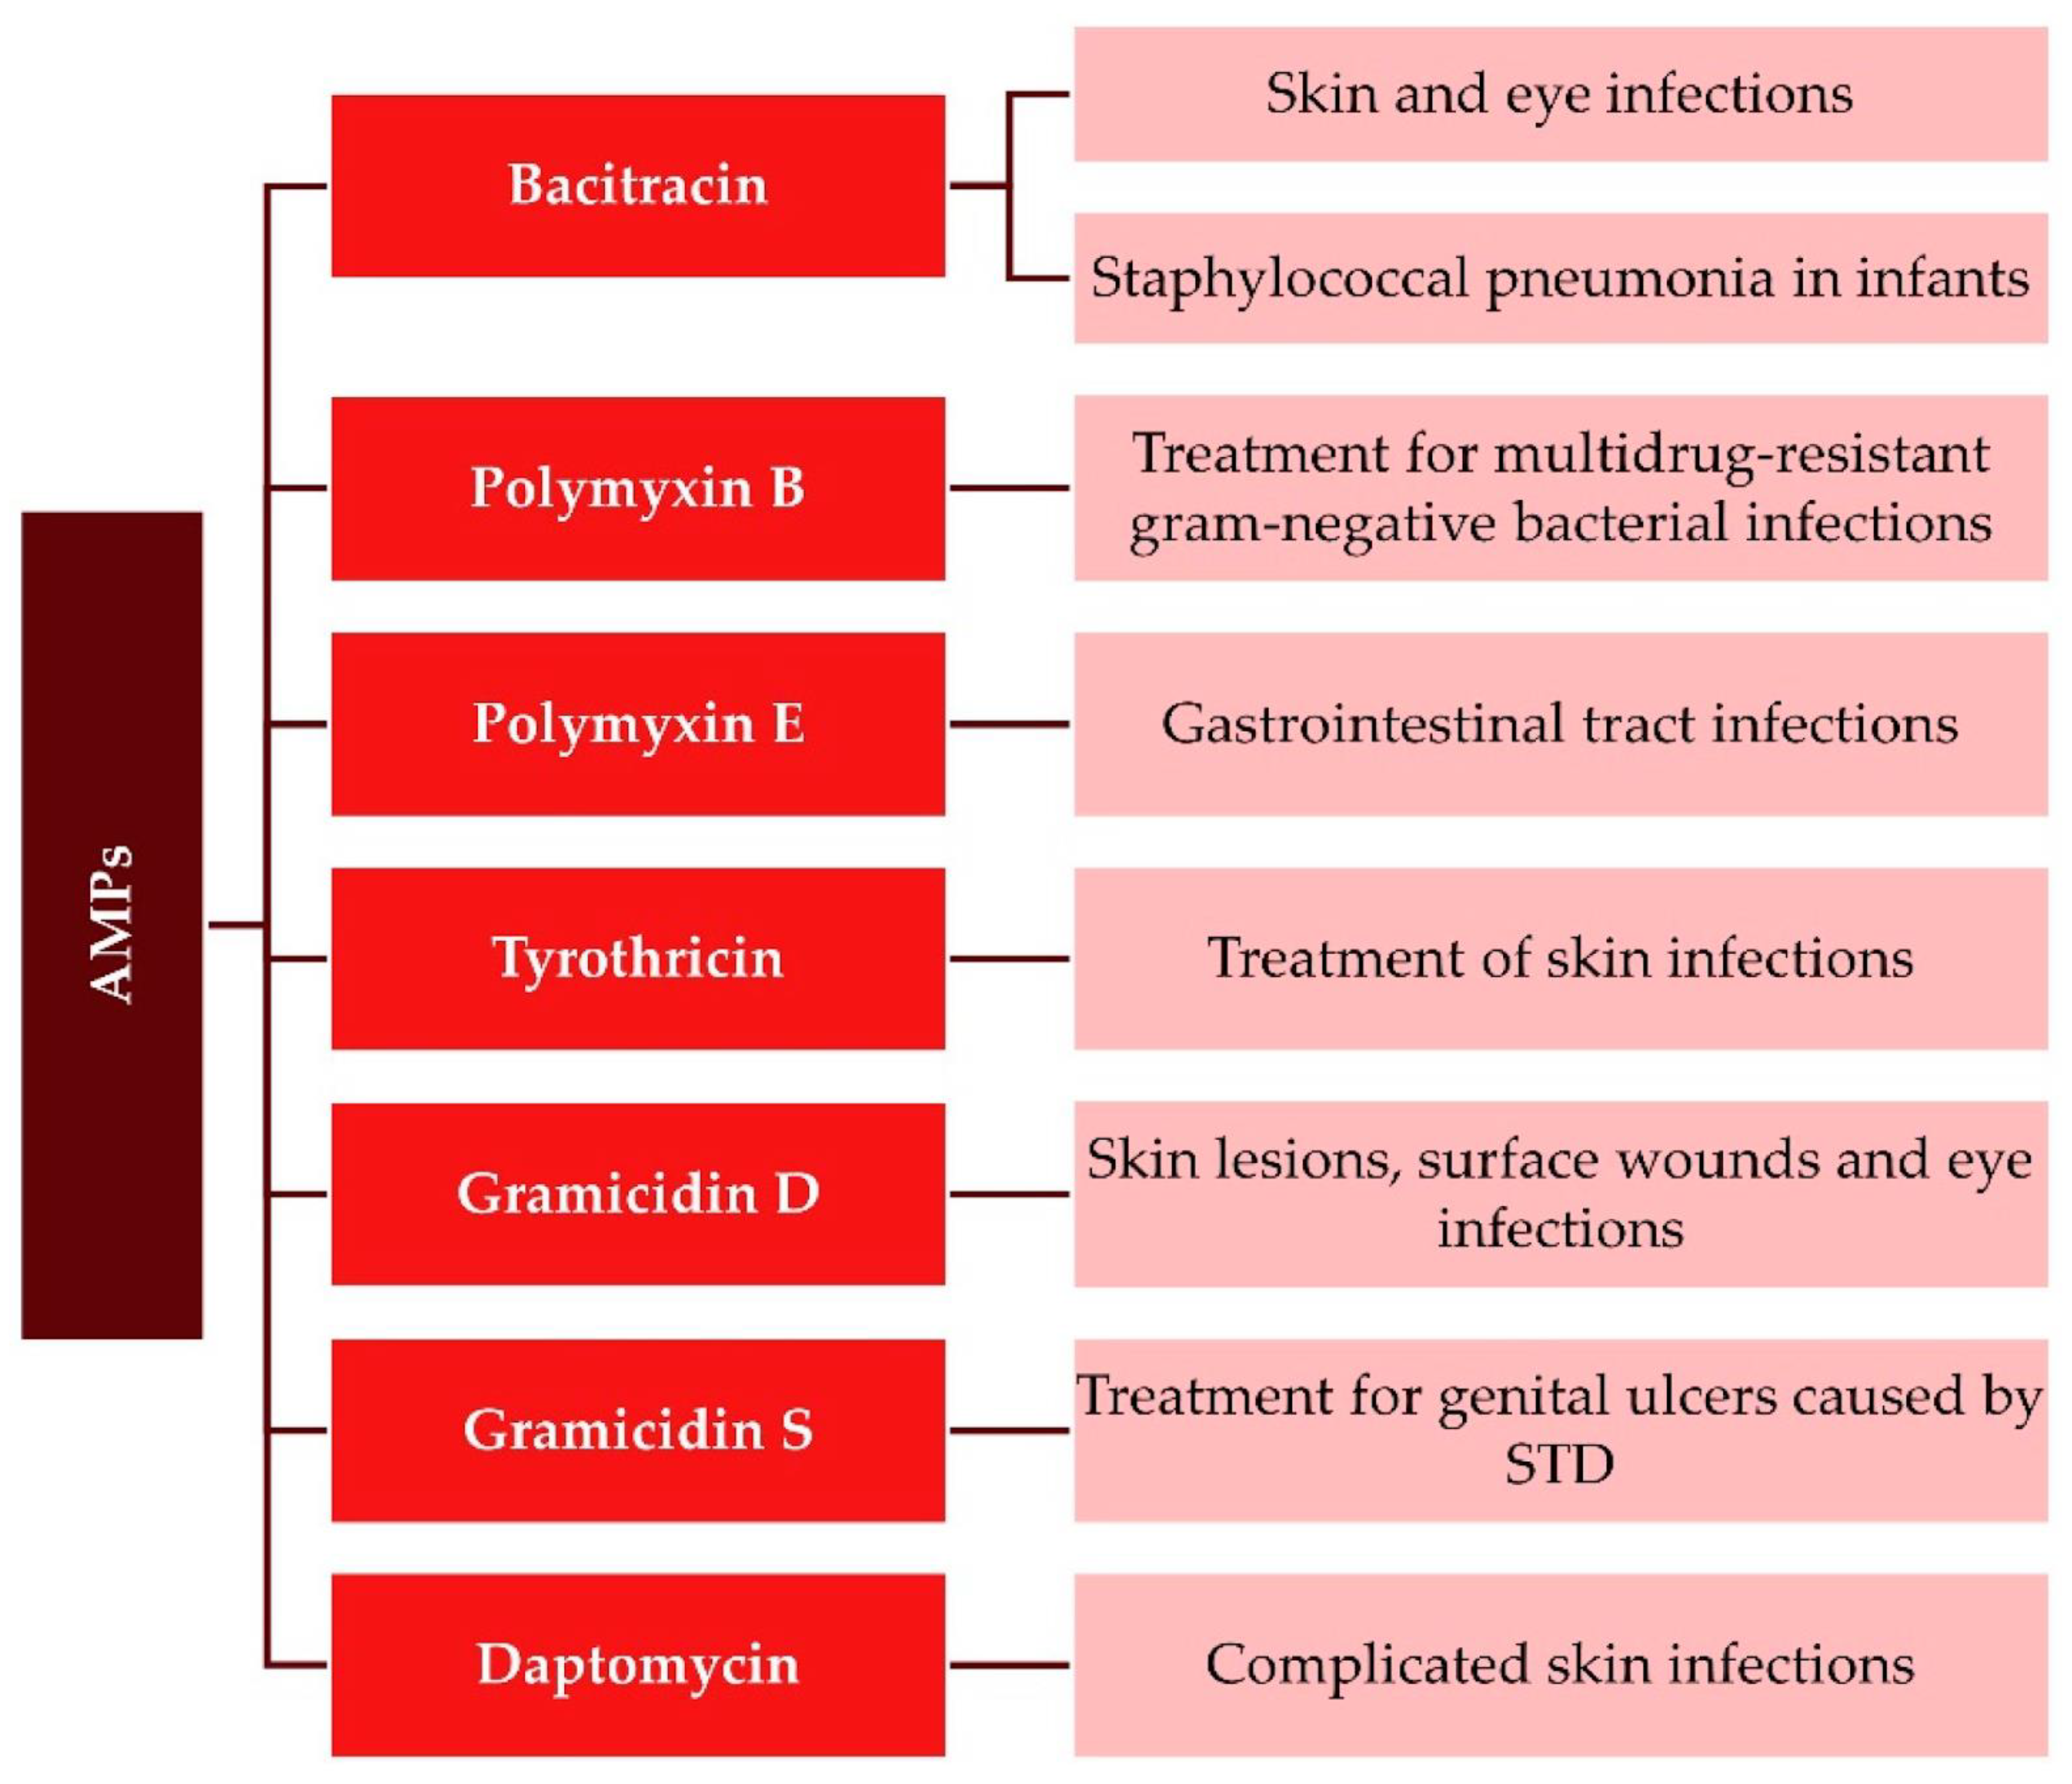

1. Introducing Antimicrobial Peptides in Pharmacology